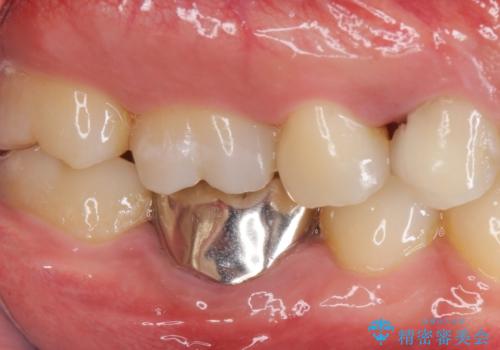

- 右上4 253,000円(部分矯正(エクストリュージョン):110,000円 歯周外科治療:エクストリュージョン代に含まれます 根管治療:保険 ファイバーコア:22,000円 仮歯:11,000円 ジルコニアクラウン:110,000円)費用は治療当時の料金となります